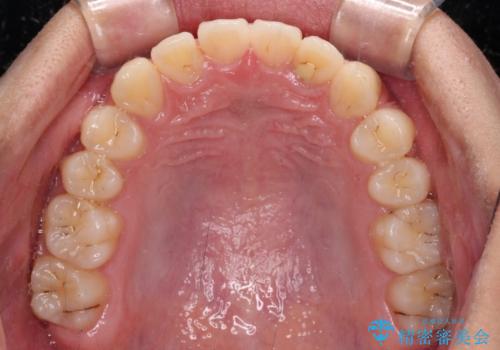

- 前歯のデコボコと隙間を気にして来院された高校生の患者様です。

下顎前歯が上顎前歯を突き上げるような咬み合わせとなっており、その影響で上顎正中に隙間ができている状態でした。

叢生の程度は軽度であり、本人もしっかりと使用する自信があるとのことだったので、インビザラインによる矯正治療を行うこととしました。

突き上げによる隙間を予防する為に、深い咬み合わせを改善するような治療計画としました。咬み合わせを改善させることはできましたが、隙間は後戻りしやすいので、通常の下顎前歯のみではなく、上顎前歯2本もワイヤーで保定を行いました。